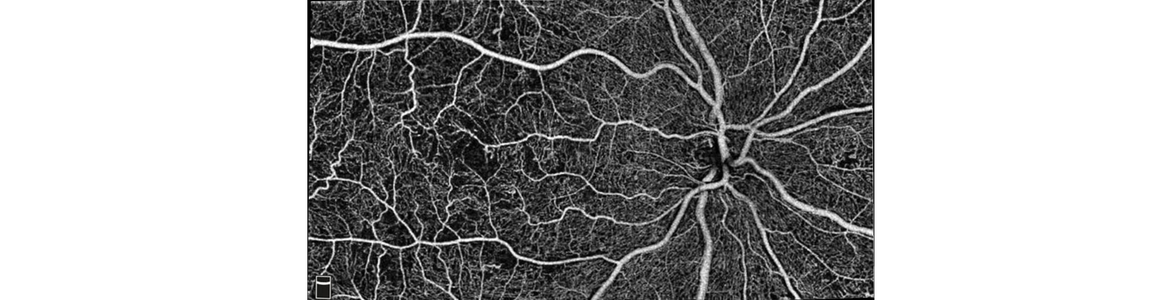

In a single image both the vitreous and the chorioid reveal in a crystalline way. The Topcon DRI-OCT strengthens the illustration of the exterior structures of the retina and the deep pathological findings. The Topcon DRI-OCT Triton automatically detects 7 layers including the one of the sclerachorioid boundary. The B-Scan 12mm covers the area of the macula as well as the optic disc.